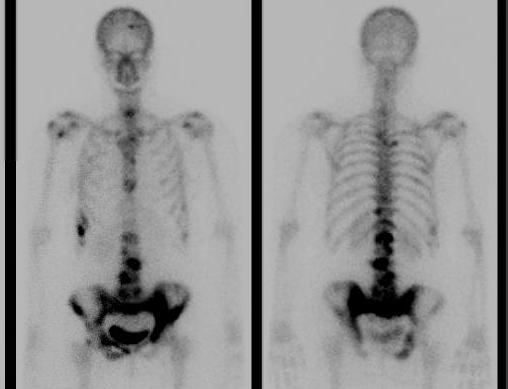

11. Superscan

Metabolic bone disease

- osteomalacia

- hyperparathyroidism

- enal osteodystrophy

Myelofibrosis

Disseminating coalescing metastasis